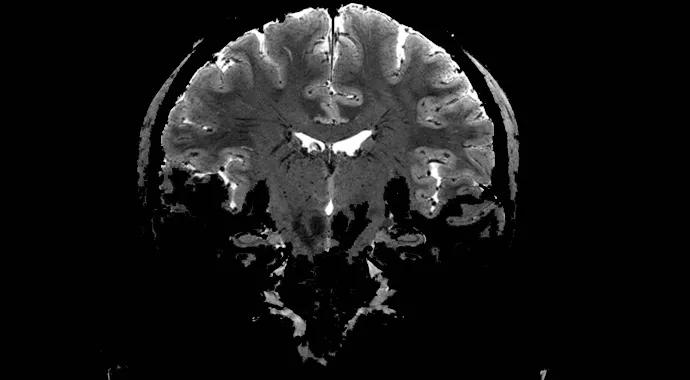

7T MRI scanners enable system-level brain study at near-microscopic scale

Cleveland Clinic recently installed a 7-tesla MRI scanner on its main campus, making it one of only 13 medical centers in the United States with 7T MRI scanning abilities.

The new scanner’s more than doubling in field strength (relative to the previous 3T standard) permits researchers to produce in vivo body images at spatial resolutions up to five times greater than those possible at clinical field strengths. Its images can approach the spatial resolution of CT scans while maintaining the superior soft-tissue contrast of MRI.

Extremely high-resolution diffusion tensor imaging of the hippocampus with the 7T scanner may permit discovery of novel biomarkers in Alzheimer disease and other cognitive disorders.